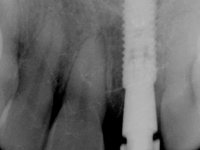

A paciente apresenta um desvio da linha média superior de 6 mm para a esquerda. Resultado da ausência do incisivo central superior esquerdo, os dentes adjacentes inclinaram mesialmente para esta zona, limitando o espaço disponível para a reabilitação prostodontica. Existe uma significativa desarmonia dentária negativa no arco maxilar como resultado da ausência do 21, ausência do primeiro pre-molar com um espaço residual, significativa redução coronária do segundo pre-molar direito, migração dos dentes posteriores para os espaços não preenchidos e uma mesialização molar superior esquerda e direita com uma relação molar em Classe II. Ambos os caninos esquerdo e direito mostram uma relação Classe II na posição de inter-cuspidação máxima. A paciente apresenta uma linha de sorriso média, um biótipo gengival médio grosso, apresenta uma correcta higiene oral sem doença periodontal. Não apresenta hábitos para –funcionais. O exame radiográfico mostra uma significativa inclinação dos eixos dos dentes 11 e 22 com espaço entre a porção apical das raízes. A análise cefalométrica foi feita com o intuito de explorar a hipótese de conseguir arranjar espaço para a colocação de um implante e de uma coroa no local do dente 21. Finalmente a morfologia do osso residual presente na região anterior da maxila foi avaliado com uma TAC, revelando uma perda das dimensões da parede óssea vestibular.